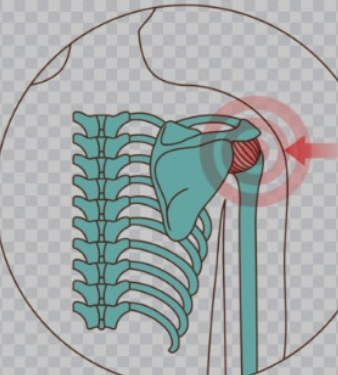

안녕하세요, 여러분! 요즘 어깨 통증으로 인해 일상생활이 불편하시지는 않나요? 50견(오십견)은 어깨 관절의 유착으로 인해 발생하는 질환으로, 초기에는 가벼운 통증이지만 점차 팔을 올리거나 뒤로 젖히는 것이 힘들어질 수 있습니다. 저도 한때 팔을 들어 올리기조차 어려웠던 경험이 있어서 그 고통을 잘 알고 있습니다. 하지만 다행히도 꾸준한 스트레칭을 통해 어깨의 가동 범위를 회복하고 통증을 완화할 수 있습니다. 오늘은 50견을 극복하는 데 효과적인 스트레칭 방법을 소개해 드릴 테니, 함께 건강한 어깨를 되찾아 봅시다!

전방 겨드랑이 스트레칭은 굳어진 어깨를 부드럽게 풀어주는 데 도움을 주는 운동입니다. 특히 팔을 앞으로 올리기 어려운 경우 이 스트레칭이 효과적입니다.